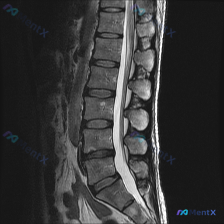

网上看到一份腰椎MRI T2序列的矢状位影像,用户第一句问的是「有没有脊柱侧弯」。 先不说结论,把影像里能看到的客观表现先列出来: - 下腰椎(L4/5、L5/S1)椎间盘T2信号明显降低,高度稍变窄,后缘有突向椎管的局限性影,压迫硬膜囊前缘; - 部分椎体终板有T2高信号,考虑Modic改变; -...

网上看到一份病例的影像讨论: 有人拿了一张腰椎矢状位T2加权MRI直接问「这张图有没有脊柱侧弯(Scoliosis)」。 先不说结论,先整理下这张图的主要影像表现: 1. 椎间盘:L3/L4、L4/L5、L5/S1信号明显降低(黑盘),L4/L5、L5/S1椎间隙轻度变窄,且这两个节段有明确的后方突...

整理到一份影像读片的病例资料,觉得很容易踩「诊断维度错位」的坑,放出来讨论一下。 先看核心情况: - 疑问是「从这张MRI能不能看到脊柱侧弯」 - 提供的是腰椎MRI T2加权矢状位图像 先附影像报告里的客观表现: 1. 椎间盘:腰椎各节段T2信号明显降低(脱水退变),L4/L5、L5/S1椎间隙狭...